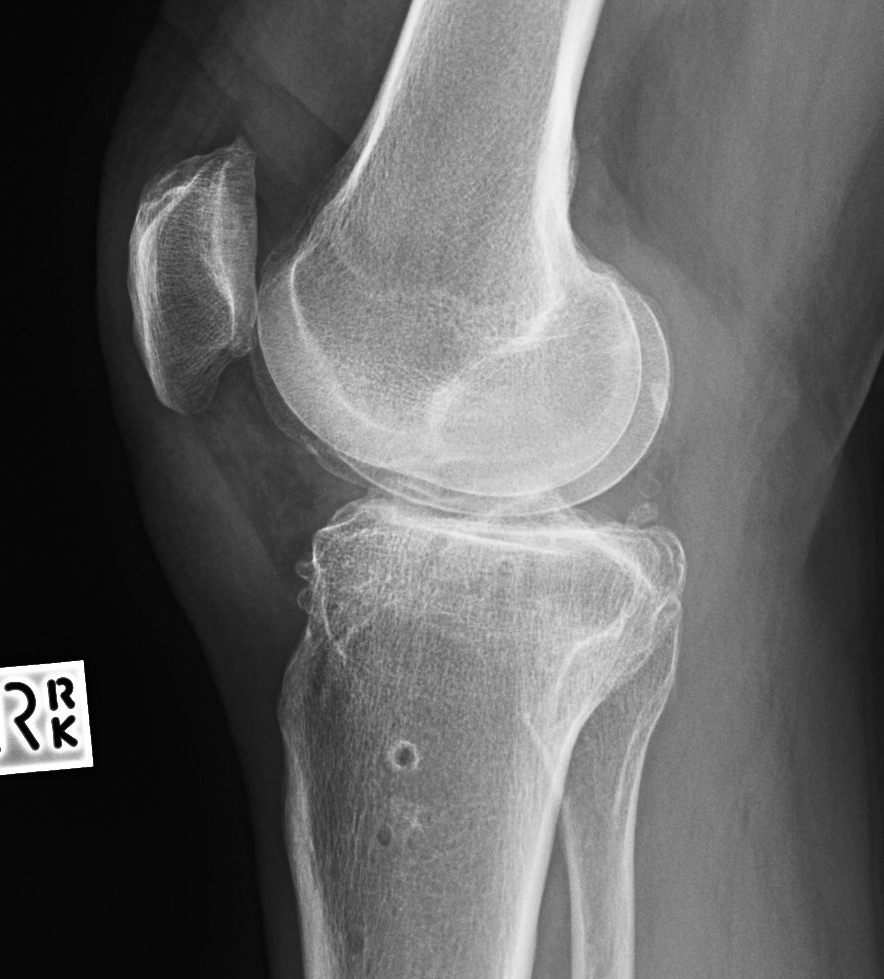

1. Decreased tibial bone stock

Lateral closing wedge

- loss of lateral bone stock

- may rarely need augments

2. Anterior tibial slope

Due to incomplete posterior osteotomy closure

- need to be aware

- ensure correct slope with bone cuts